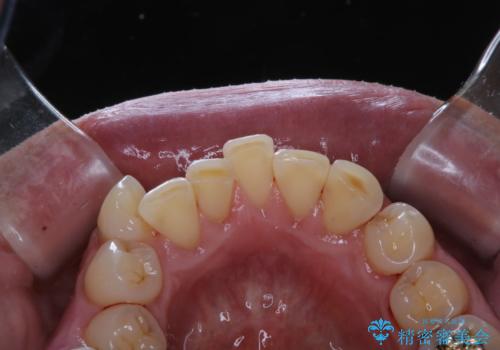

被せ物治療が終了したため全体的にクリーニングを

- 被せ物の治療が終了したためメンテナンスに入る前に全体的なチェック・クリーニングを行いました。

歯科衛生士による専門的なクリーニングPMTC(保険外治療)60分コースを行いました。

専門的な機械・材料を使用して徹底的に汚れを取り除きました。

治療が終了したら、そこで終わりではなく、そこからのケアがとても大切です。

いくら綺麗なセラミックがセットされても、歯ブラシが適切にできないと汚れが付着します。治療が終わったら、改めて現状のお口の中に合わせたブラッシング指導を行い長期的に安定したお口の環境づくりにしていきます。